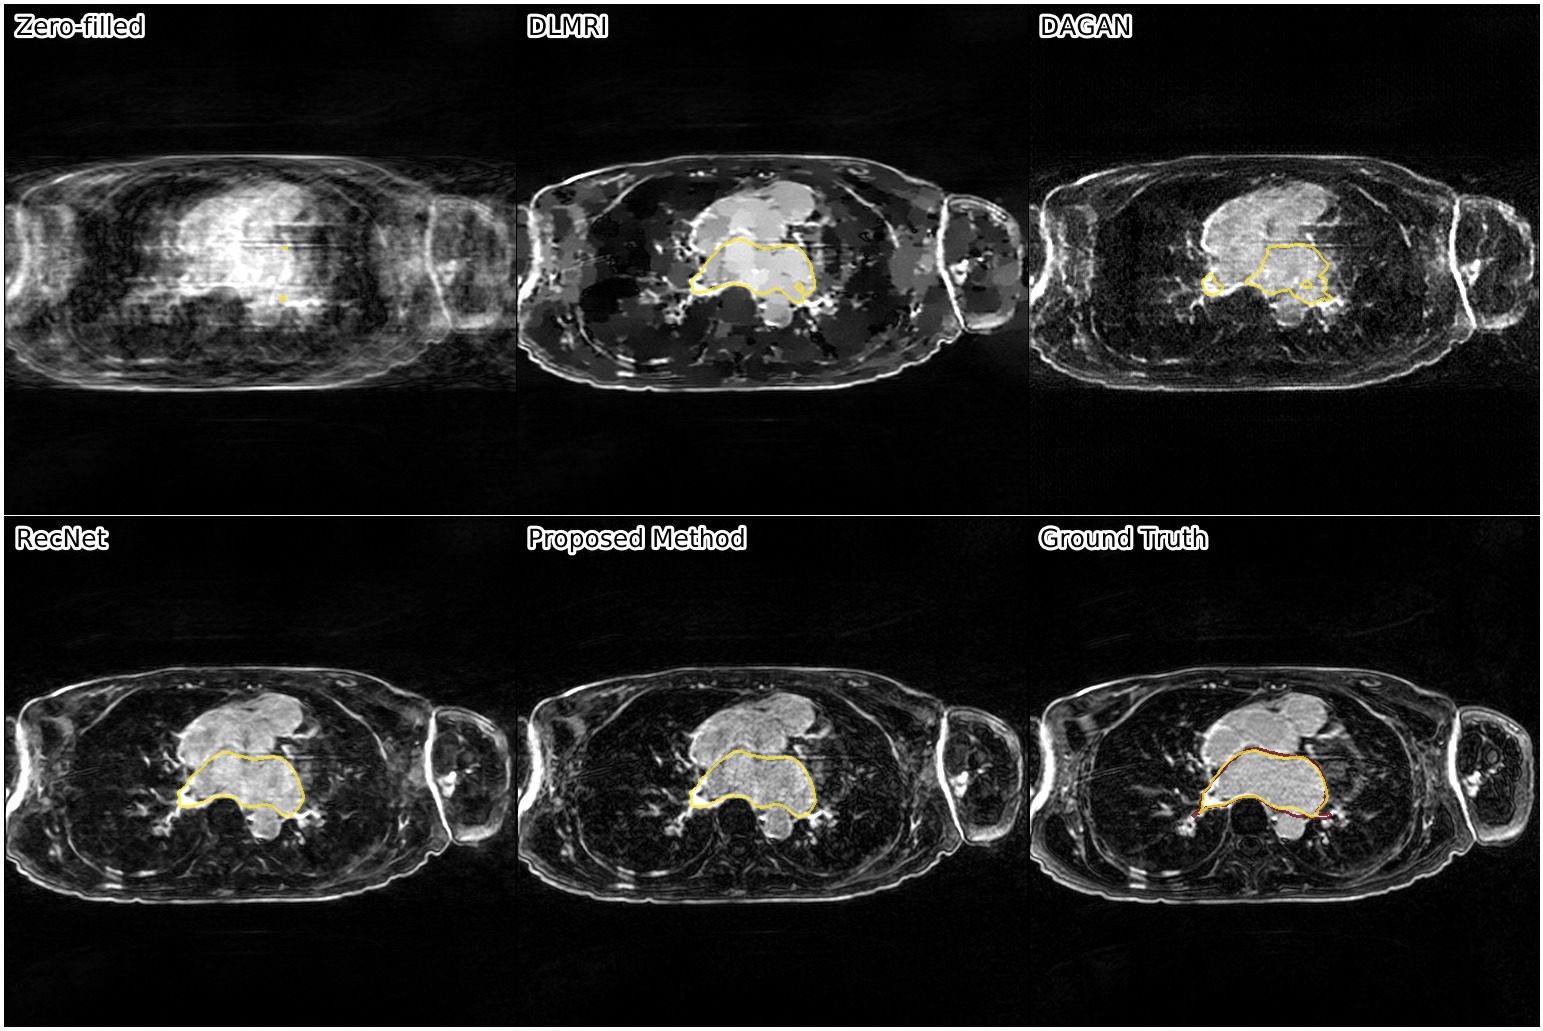

Results. We compared our approach against three other reconstruction methods: RecNet111https://github.com/js3611/Deep-MRI-Reconstruction [14] (i.e. the proposed approach without refinement step), DAGAN222https://github.com/nebulaV/DAGAN [16] using both adversarial and perceptual loss, and DLMRI333http://www.ifp.illinois.edu/~yoram/DLMRI-Lab/DLMRI.html [10], a dictionary learning based method. No data augmentation was used for any of the methods.

We show the results of our evaluation in Table 1, and a sample reconstruction in Figure 2. RecNet performed best in terms of PSNR, which is expected as its training objective directly corresponds to this metric, but its reconstructions were over-smoothed. DLMRI had the lowest MOS, with its reconstructions showing heavy oil paint artifacts. DAGAN, combining MSE loss with a visual loss function without any further precautions, suffered from low PSNR. While its reconstructions also looked sharp, they were noisy and often displayed aliasing artifacts, which was reflected in a lower MOS compared to our method. Our proposed approach achieved significantly444Significance determined by a two-sided paired Wilcoxon signed-rank test at . higher mean opinion score than all other methods, while still maintaining high PSNR. Reconstructions obtained by our method appeared sharper with better contrast. Moreover, our method achieved the highest SIS close to segmentation performance on the ground truth data, which indicated that the segmented objects were clearly visible in the reconstructed images.

These results further demonstrate that PSNR alone is a subpar indicator for reconstruction quality, making our SIS a useful supplement to those metrics. For our method, SIS agreed with the quality score given by the expert user. Somewhat surprising is that the SIS of DLMRI is slightly higher than RecNet and DAGAN although DLMRI has the worst MOS. We conjecture this is because, although DLMRI reconstructed images lack textural details, areas belonging to the same organ have similar intensity values, which helps the segmentation task. While scoring through an expert user is thus still the safest way to evaluate reconstructions, we believe that in conjunction with PSNR, SIS is a helpful tool to quickly judge image quality during the development of new models.

The following images show more samples for 8-fold undersampling. For each of the seven patients of the test set, a random slice showing the left atrium was selected. The contour of the predicted segmentation of left atrium is shown in yellow, the contour of the ground truth segmentation in red.